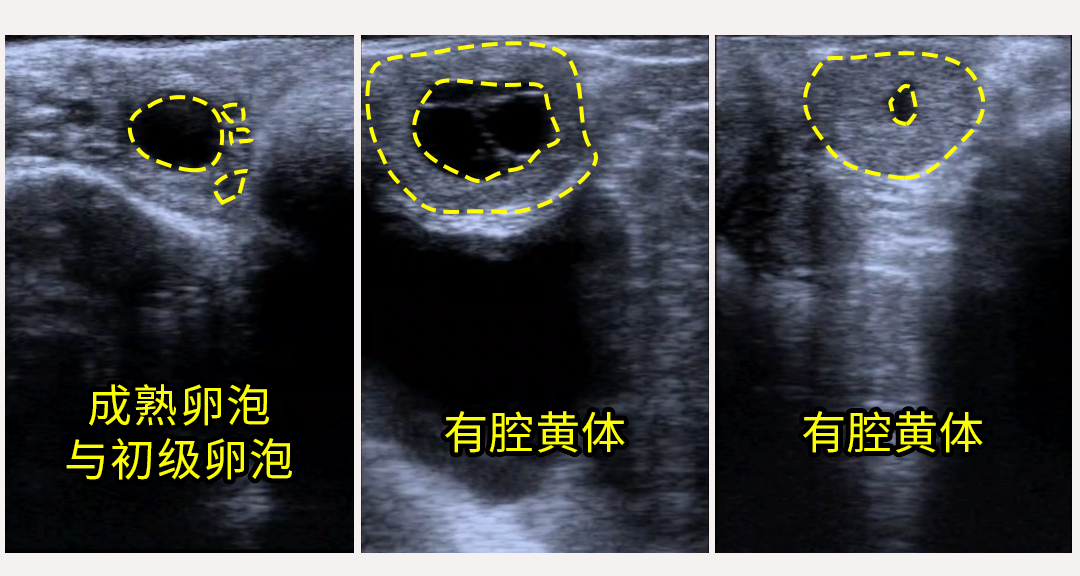

母牛的卵泡在发育过程中会逐渐增大,在B超图像上表现为边界清晰、内部为黑色液性暗区的圆形结构。不同发育阶段的卵泡,直径存在差异:

卵泡排卵后,残余组织会形成黄体。黄体的主要作用是分泌孕酮(黄体酮),为受精卵着床和维持妊娠提供必需条件。

在B超图像中,黄体通常表现为灰白色或混合回声团块,有些黄体内部会出现不规则的腔隙。如果使用彩色多普勒功能,还可以观察到黄体内部和周围的血流情况: